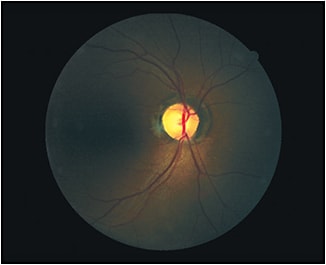

BCVA was 20/50 OD and 20/30 OS. Extraocular muscles were full, smooth and without restriction. Pupils were equal, round, reactive and had no afferent pupillary defect. IOP was 12mm Hg OD and OS. Anterior slit lamp exam was unremarkable. Dilated fundus exam revealed bitemporal optic nerve pallor with a c/d ratio of .5/.5 OU. Maculae were flat and evenly pigmented. Peripheral retinal exam did not reveal any evidence of pathology.